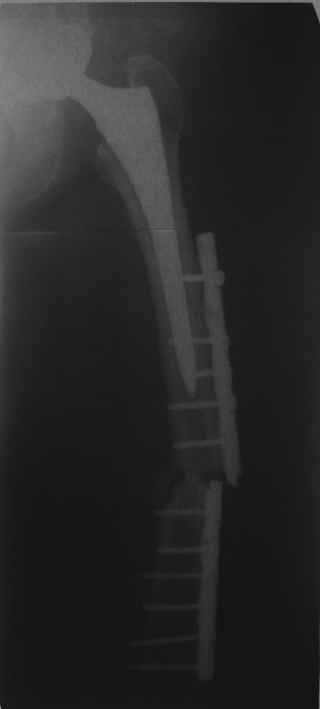

Re: Перипротезный перелом

Обещанные ранее снимки Заранее спасибо.